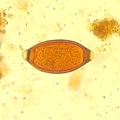

Bildquiz Antwort % Korrekt

Ascaris lumbricoides

100%